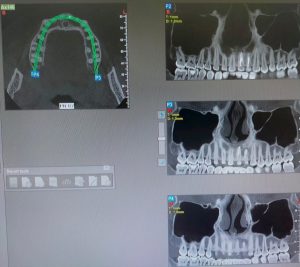

Cone beam

CONEBEAM ou CBCT (cone beam computerised tomography)

C’est une technique utilisant les rayons X avec acquisition 3D permettant d’étudier les dents dans les différents plans de l’espace.

Sa résolution est supérieure à celle d’un scanner, tout en étant beaucoup moins irradiant et moins sensible aux artéfacts dus aux couronnes ou aux implants.

Le CBCT est utilisé dans de nombreuses indications d’odonto-stomatologie et de chirurgie maxillo-faciale.

Il peut être réalisé avant extraction des dents de sagesse, en cas de dent incluse, de dent surnuméraire, pour étudier au mieux les inflammations péri-dentaires et les rapports avec les sinus maxillaires…

Cet examen permet aussi de rechercher et d’identifier plus précisément les fêlures radiculaires et les lésions osseuses (ostéonécrose / lésions kystiques/ lésions tumorales).

Il permet un repérage très précis des structures anatomiques grâce à des reconstructions multiplanaires et volumiques. Ainsi, en implantologie, il permet de positionner les implants avec précision.

L’examen est rapide et parfaitement indolore. Selon le type d’appareil, vous serez placé en position semi couchée ou debout.

L’acquisition des images ne dure que quelques secondes pendant lesquelles il faudra rester immobile.

Ces images seront ensuite retravaillées sur une console dédiée (post-traitement) en fonction des indications et des demandes des prescripteurs. Elles seront analysées par un radiologue spécialisé dans l’imagerie dentaire avec production d’un compte rendu.